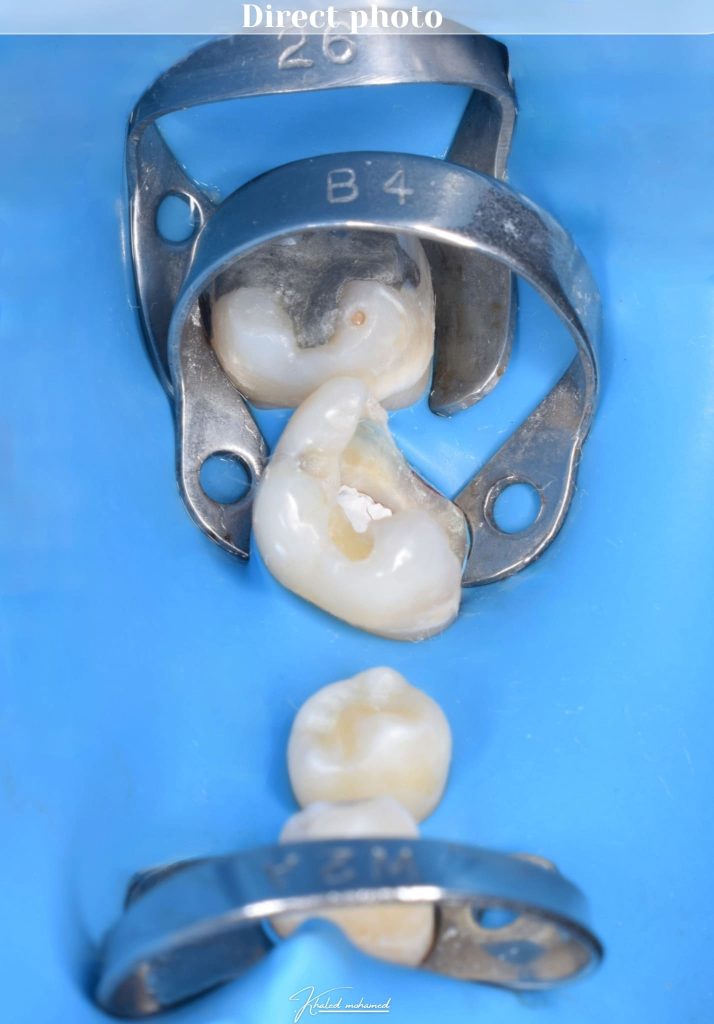

Multiple isolation

Direct view for isolation

B4 in action